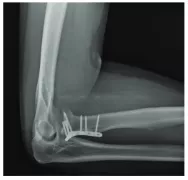

Where a large bone fragment has moved out of its regular place, a metal plate and screws may be necessary to join it back.

Type III fractures are the most severe kind of radial head injuries.

They produce multiple bone splinters that can make bone restoration almost impossible. In most cases, the damage extends to the ligaments, nerves, and other structures surrounding the elbow joint.

Type III fractures typically call for major surgery.

The surgeon may either remove the broken fragments altogether or, if possible, try to fix it by putting them back together. If the removal of the radial head is necessary, an artificial unit may be installed in its place.

This is a permanent treatment and can restore a degree of movement, ensuring long-term joint operation.